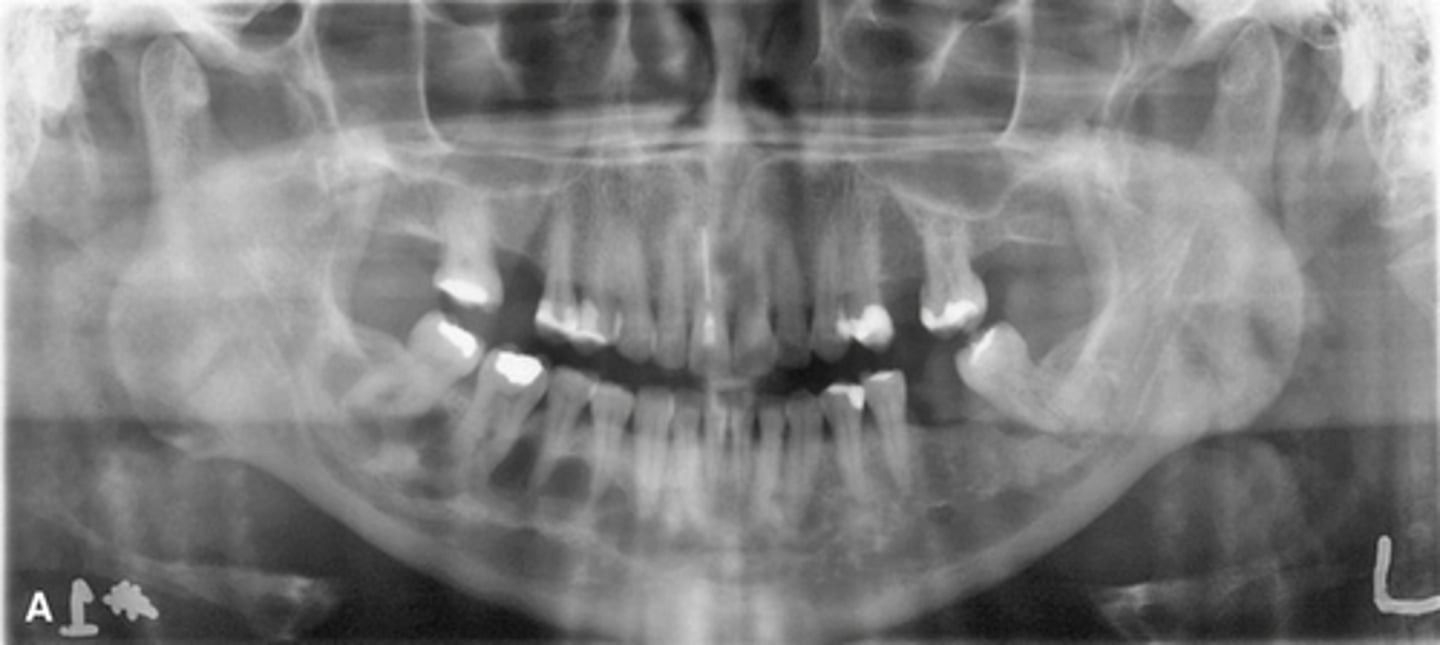

Patient has DJD, there is significant erosion and loss of joint space.

A and B show prominent osteophyte formation at the anterior aspect

C shows multiple subchondral erosions

What is the diagnosis of the patient based off these radiographs and what are the features?